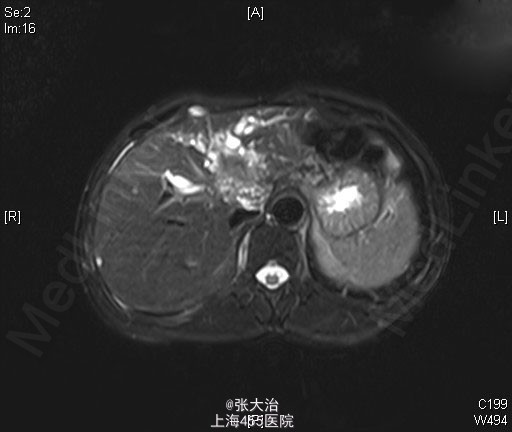

查体:神志清晰,精神尚可,呼吸平稳,营养中等,表情自如,发育正常,自主体位,应答流畅,查体合作。全身皮肤无黄染,无肝掌、蜘蛛痣。全身浅表淋巴结无肿大,无明显贫血貌,左锁骨上淋巴结(-);腹部平坦,未见肠型或胃蠕动波,未见腹壁静脉曲张;全腹软,无压痛、反跳痛、肌紧张。肝脾肋下未及,包块未及;移动性浊音(-),肠鸣音正常,每分钟约3次,不伴高调音、气过水声。 2014-4-10某人民医院就B超(92301):肝囊肿,左肝内胆管扩张;MRI(1697647):肝门区病变可能伴左肝内胆管扩张。 2014-4-22某人民医院MRCP(68941):肝门处占位伴肝内胆管扩张,考虑胆管细胞癌可能大,肝多发囊肿。 肝动脉CTA、门脉CTV、肝静脉CTV、下腔静脉CTVCT【2014-05-05 我院】 :肝门区MT,肝左、右动脉及门脉主干、左支受侵;肝及双肾小囊肿。 上腹部平扫+增强+DWI+MRCPMRI【2014-05-06 我院】 :肝左叶MT(胆管细胞型机会大)伴肝左叶胆管扩张,门脉受侵;肝、双肾小囊肿。 肝脾及门脉;胆(含胆总管);肾+输尿管;胰超声【2014-05-05 我院】 :超声造影:肝门部偏左侧实质占位--考虑肝门部胆管MT,侵犯门脉左支可能;肝左叶胆管扩张;右肾囊肿 肝脏超声造影超声【2014-05-05 我院】 :超声造影:肝门部偏左侧实质占位--考虑肝门部胆管MT,侵犯门脉左支可能;肝左叶胆管扩张;右肾囊肿 肝脏术后(检查胸水、腹水、手术区、膈下)超声【2014-05-20 我院】 :右侧胸腔少量积液;腹水